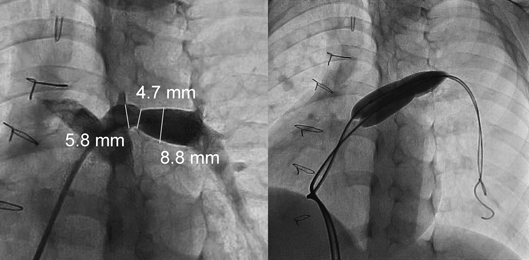

バルーンサイズ選択は血管造影に基づくため,事前の血管造影は参照画像として重要である.バイプレーンアンギオ装置を使用して狭窄部描出が最良となるよう個別に撮像角度を調整する.例えば左肺動脈狭窄や右肺動脈狭窄においては正面カメラをそれぞれ左斜位や右斜位とするとともに頭側・尾側へ調整して撮像することでも狭窄部を的確に描出することができる(Fig. 3).血管造影により撮像された画像から最狭窄部とその前後の(狭窄していない)参照血管径の3か所を計測する(Fig. 4).肺動脈狭窄においては経胸壁心エコー図での詳細な描出は困難なことも多いため病変の特定や形態は血管造影に委ねられる.経皮的血管形成術における放射線面積線量積は約1,500 μGym2と報告され心房中隔欠損や動脈管閉鎖等の他の先天性心疾患カテーテル治療と比較して有意に多い20).そのため「as low as reasonably achievableの原則」により放射線被ばく低減のための努力が必要であり,手技中の撮像範囲の制限,フレームレート低減または低線量撮像後のコンピュータ画像処理による工夫が推奨される.被ばくを伴わない血管内超音波検査は血管断面から血管径測定や血管壁構造の観察を可能とし21),心臓MRI検査も有力な画像診断方法として期待される22)

Pediatric Cardiology and Cardiac Surgery 38(3): 147-157 (2022)

Fig. 4 The size of a balloon is determined according to the narrowest diameter and adjacent reference diameters. The balloon diameter is as two or three times as the narrowest diameter, but within two times of reference diameters. An angiogram shows the left pulmonary arterial stenosis in a 7-month-old patient with persistent truncus arteriosus and interrupted aortic arch. The narrowest and adjacent reference diameters are 3.2 mm, 6.0 mm, and 7.5 mm, respectively. Then, balloon angioplasty is performed using a 10-mm high-pressure balloon catheter.

Fig. 6 Angiograms show the left pulmonary arterial stenosis in a 5-year-old patient after corrective surgery of tetralogy of Fallot. The narrowest and adjacent reference diameters are 4.7 mm, 5.8 mm, and 8.8 mm, respectively. We perform double balloon angioplasty using 8-mm high-pressure balloon catheters. The estimated effective balloon diameter accounts for 13.1 mm according to the described formula.